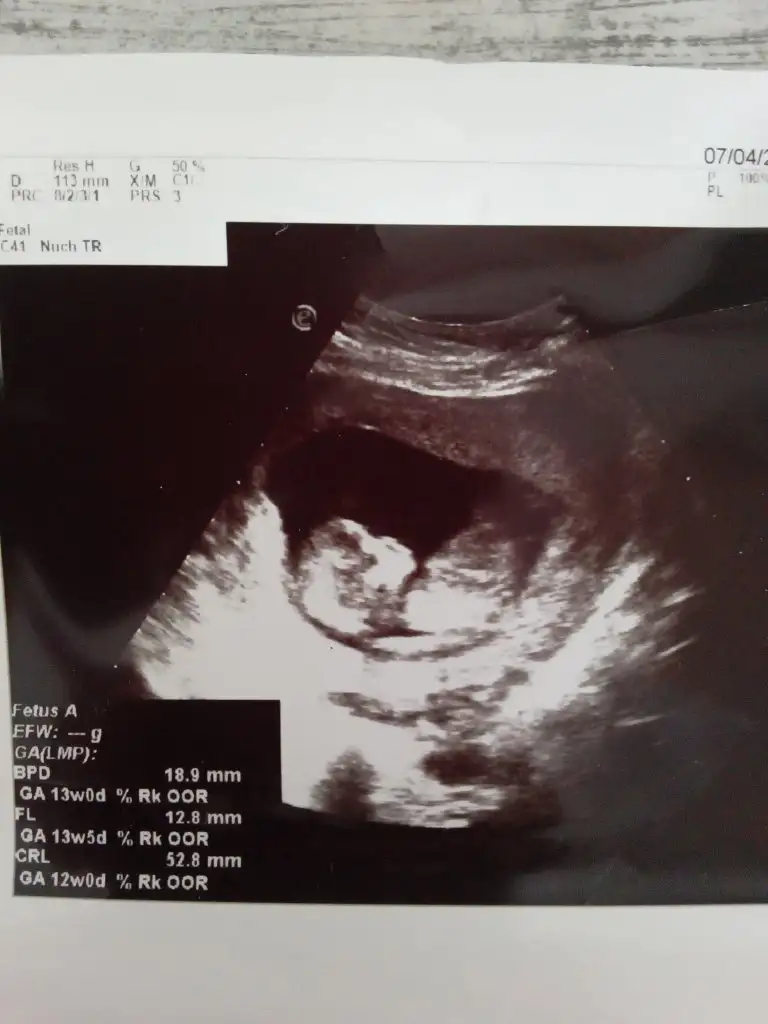

1650713735085.webp

12 haftalik karindan cekildi 1 hafta onde gidiyor 13 cikti olcumlerde 🙄ne olaki cinsiyetimiz merak ediyorum cok 🥰

Ablam hastaneye gittiğinde o kadar di şimdi haftaya göre 10 haftalık falan .ama ablam bebeği eğer küçük diyorsan bir tane oğlu var haftasına göre geriden geliyordu